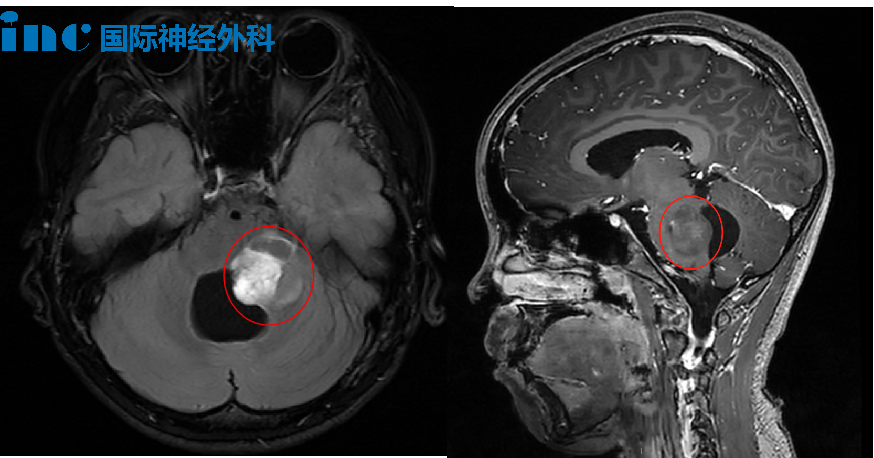

然而在了解过后,更大的绝望笼罩在茜茜父母心头:脑干是人体的“生命控制中心”,它藏在大脑深处,一度被认为是“手术禁区”,鲜有医生敢在其内部及周围实施手术,而这也成为茜茜第一次手术时的最大障碍之一。

术后,医生告诉茜茜父母,手术切除了50%左右的肿瘤,后续还要进行辅助治疗。术中的病理显示为桥脑-延髓毛细胞性星形细胞瘤,WHO 1级。

巴教授:“有明确的手术指征,我有信心完全切除肿瘤!而这意味着女孩可能被治愈!因此手术应该尽早考虑,因为等待时间过长对孩子是不利的,甚至没有任何好处。孩子有可能被治愈的机会就是尽快进行良好的手术,并且完全切除肿瘤。”

在巴教授的主刀之下,与苏州大学附属儿童医院手术团队紧密合作,一场“惊心动魄”的手术开始了。面对质地坚硬的肿瘤,巴教授以一把CUSA刀展现“肿瘤消失术”,最终手术成功,肿瘤得到全切。